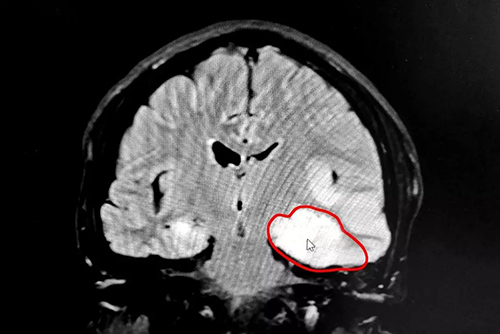

CT检查结果显示,患者头颅左侧颞枕顶叶见弥漫性大片状低密度影,其中左侧枕叶可见团块状稍高密度影,临近左侧侧脑室受压变窄,中线结构向右侧移位,其内脑沟消失,脑组织肿胀。据此,诊断患者张先生为大面积脑梗。

▲CT检查显示,患者左侧颞枕顶叶大面积脑梗